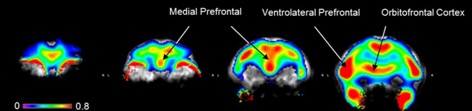

β WAY-208466, a 5-HT6 receptor agonist, increases food motivation in primates: A behavioural and PET imaging study opening perspectives in eating disorders

M. Pitoy, J. Maulavé, L. Gauthier, J. Debatisse, N. Costes, I. Mérida, T. Billard, K. Portier, S. Lancelot, B. Galusca, L. Zimmer, L. Tremblay

Neuroscience Applied 2024, 3, 104086